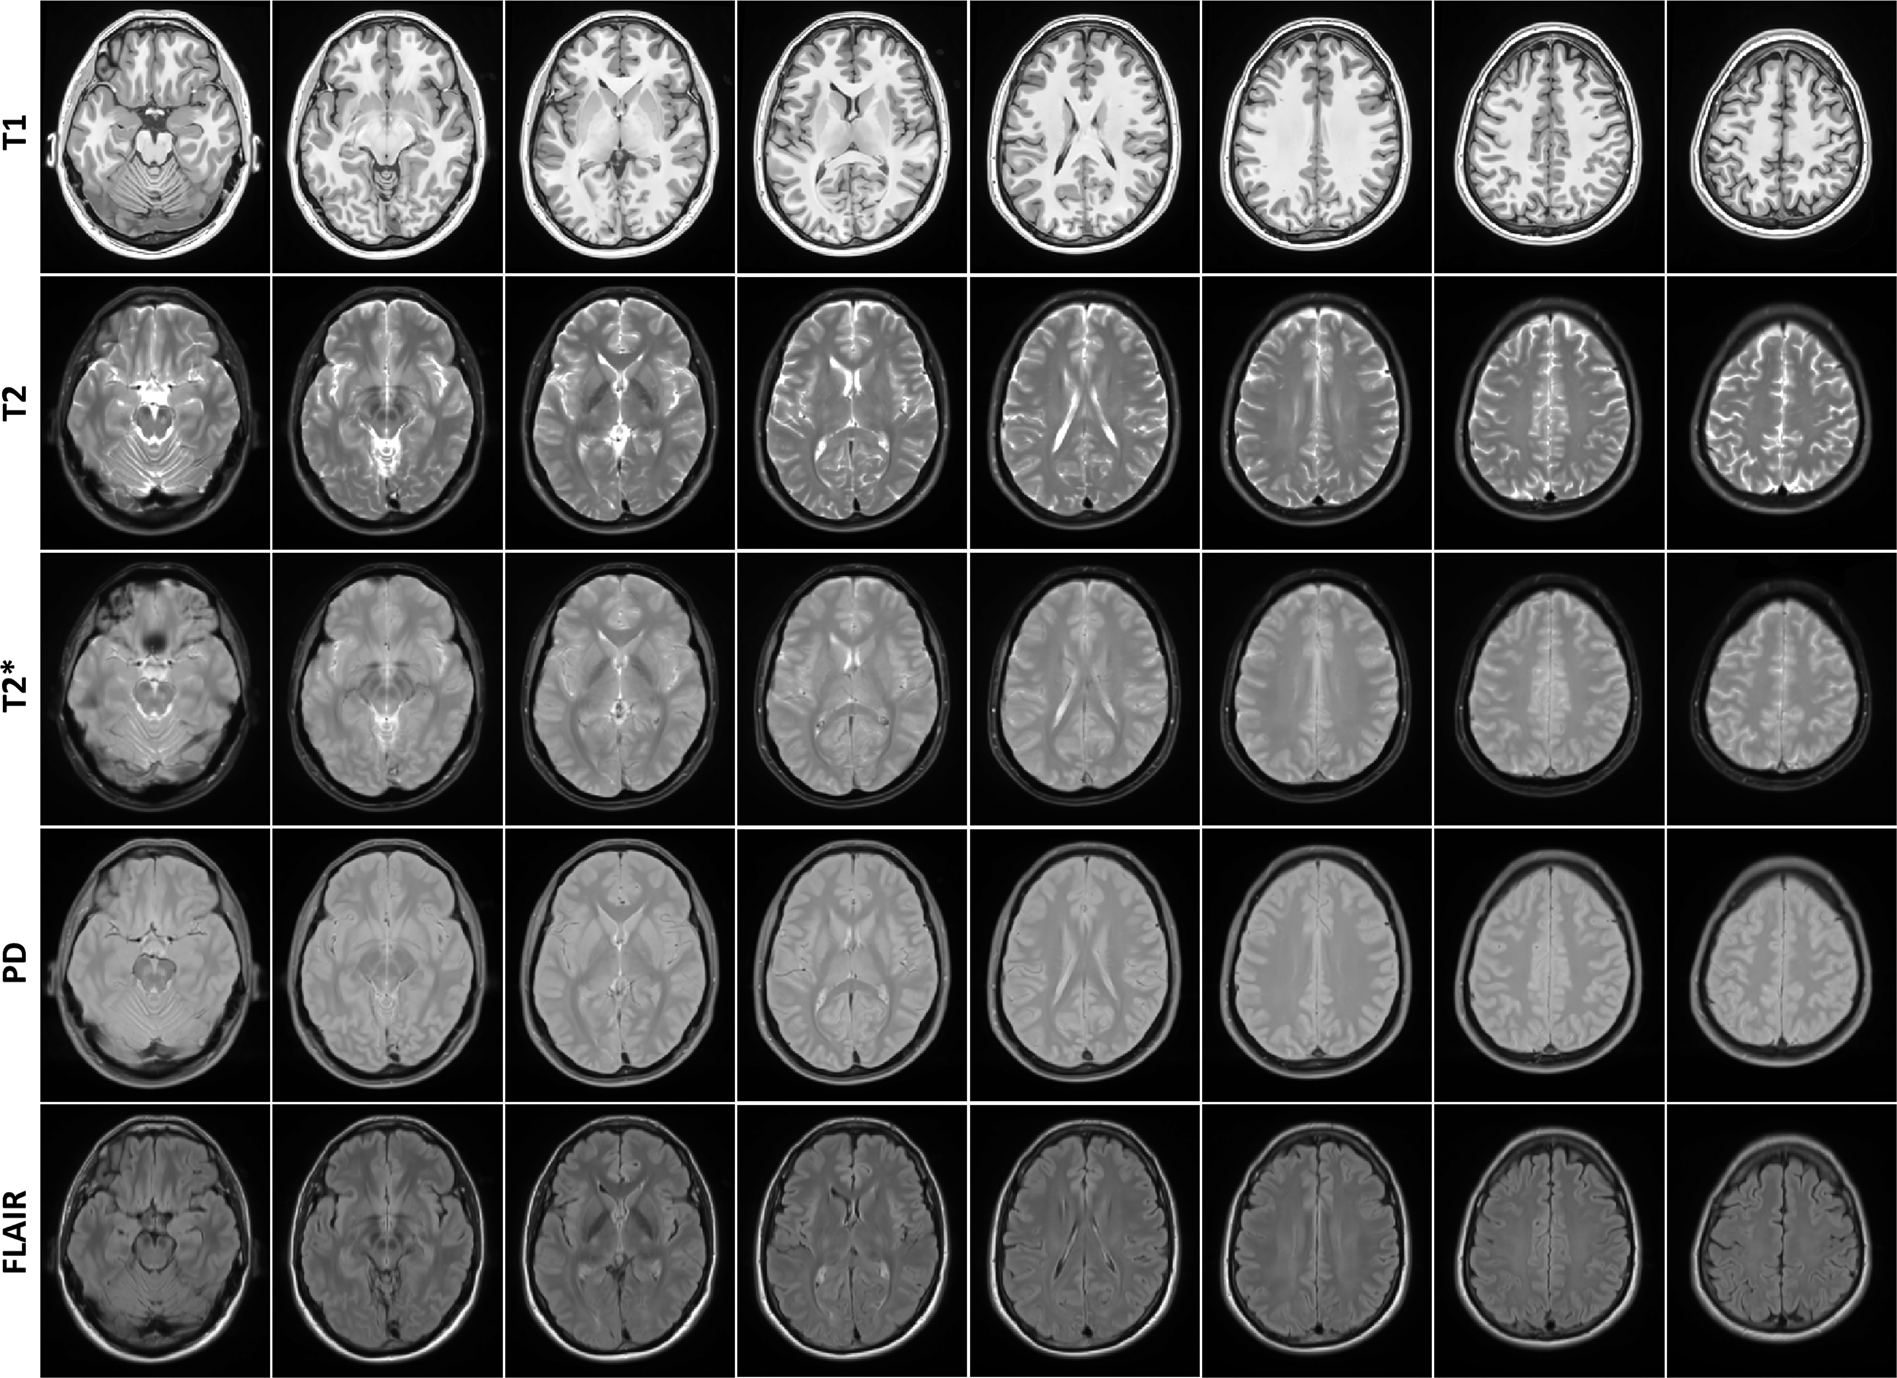

Axial slices of human phantom (SIMON) templates for all sequences.